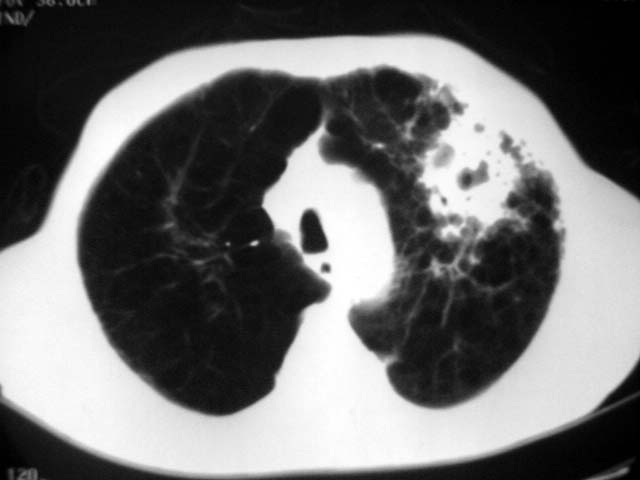

以下是引用zjzjr在2007-9-4 17:00:00的发言:[br]双上肺继发型结核伴左上肺空洞形成.慢性支气管炎伴肺气肿.

以下是引用liuzheng_9326在2007-9-4 16:23:00的发言:[br]痰检未见结核菌, 治疗后症状好转。图像符合陈旧性结核伴感染。